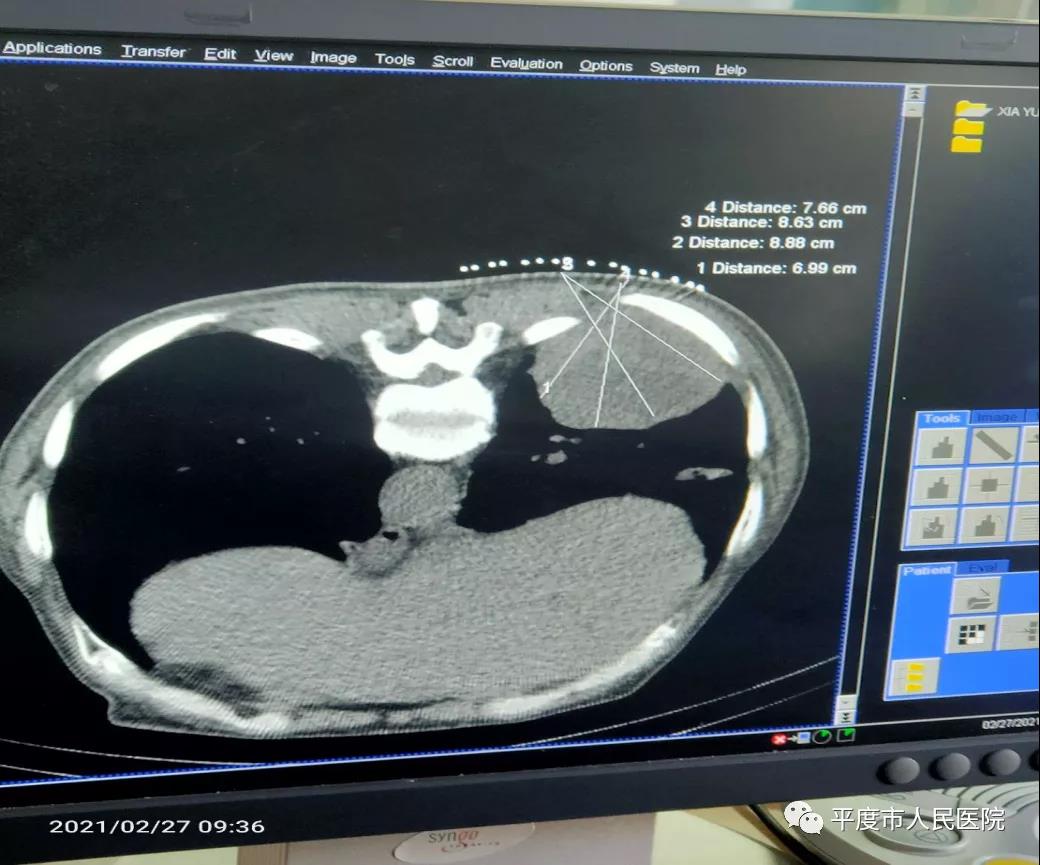

术前显示肺内的肿瘤病灶及设计的穿刺路径

患者为一老年男性,半月前出现反复发作的咳嗽来我院就诊。患者胸部CT显示右肺内肿块,大小约7.0*6.0cm,右肺门处一大小约1*2c m肿块,影像学高度怀疑为恶性病变。随即在我院介入血管外科行穿刺活检术,穿刺病理为肺鳞状细胞癌。